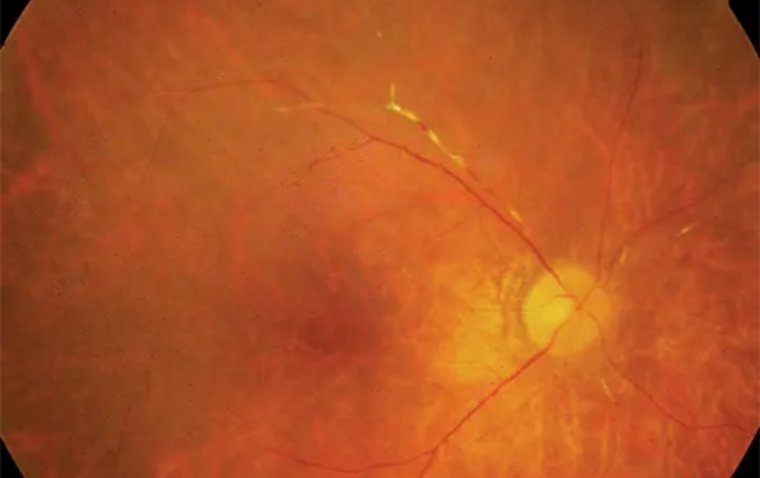

Autoimmune retinopathy presents with a range of symptoms, the most common being subacute vision loss, peripheral visual field loss, flashing lights (photopsias), and night blindness. In early stages, clinical examination may show no significant intraocular inflammation, making the diagnosis challenging. As AIR progresses, symptoms can include narrowing of the retinal vasculature, abnormalities in the retinal pigment epithelium, optic nerve pallor, and mild vitreous cells. The condition is typically bilateral, though it can manifest asymmetrically, and visual acuity is usually preserved until the disease reaches a more advanced stage.

Credit: International Journal of Retina and Vitreous